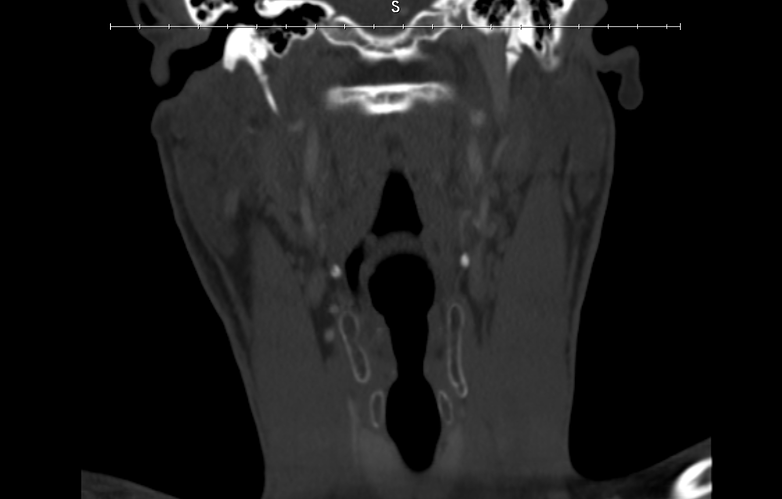

Here are my scans:

I want to get a second pair of eyes because I can clearly see the calcified ligaments he was talking about and it looks like my right IJV is being compressed but it is hard to tell. It also looks like the calcified ligament is compressing my left IJV a little bit.